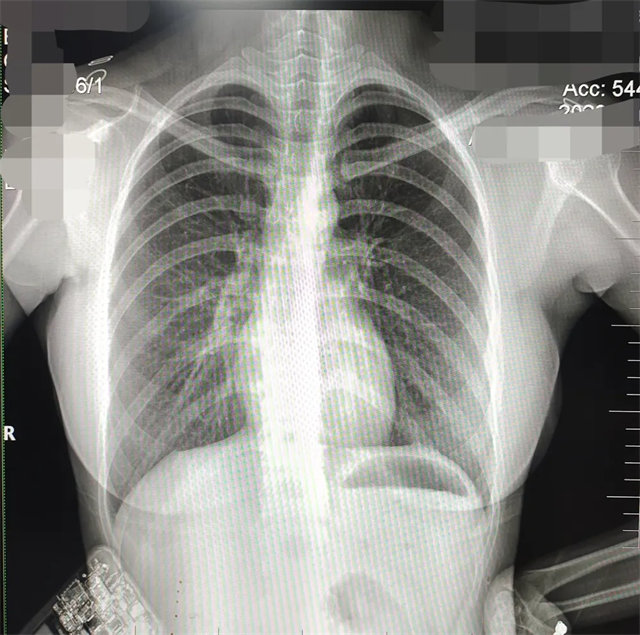

缺陷:左肩胛骨部分與左肺野重疊。

解決:使患者左肩旋前緊貼成像件重新曝光。

缺陷:肩胛骨未完全拉離肺野,吸氣不完全,存在金屬偽影遮擋,略有聳肩,且肺尖顯示不好,圖像顆粒感較強(qiáng),管電流量不夠,信噪比偏低。

解決:去除金屬物品后,按標(biāo)準(zhǔn)體位,使患者雙肩旋前與前胸一并緊貼成像件,適當(dāng)調(diào)高mAs,然后深吸氣后屏氣曝光。